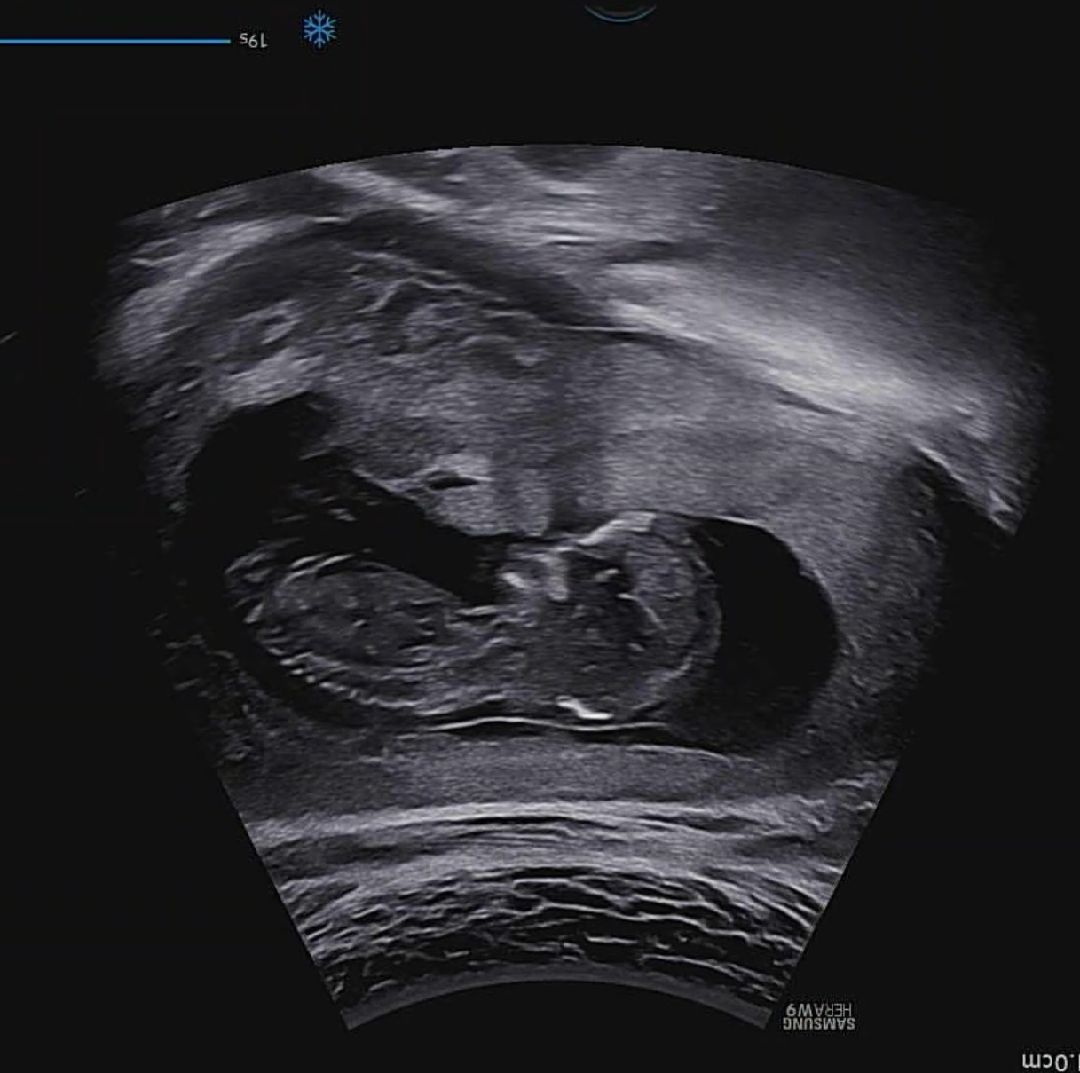

12주4일 각도법 투표부탁드려요 🙏

12주 4일 초음파 보고왔는데 각도법 한번만 봐주세요 ~!